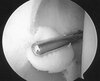

Arthroscopic image of a knee shows the posterior cruciate ligament bundle origins. The anterolateral bundle (ALB) and the posteromedial bundle (PMB) are observed at their origin on the lateral side of the medial femoral condyle (MFC), or the medial intercondylar notch.

A